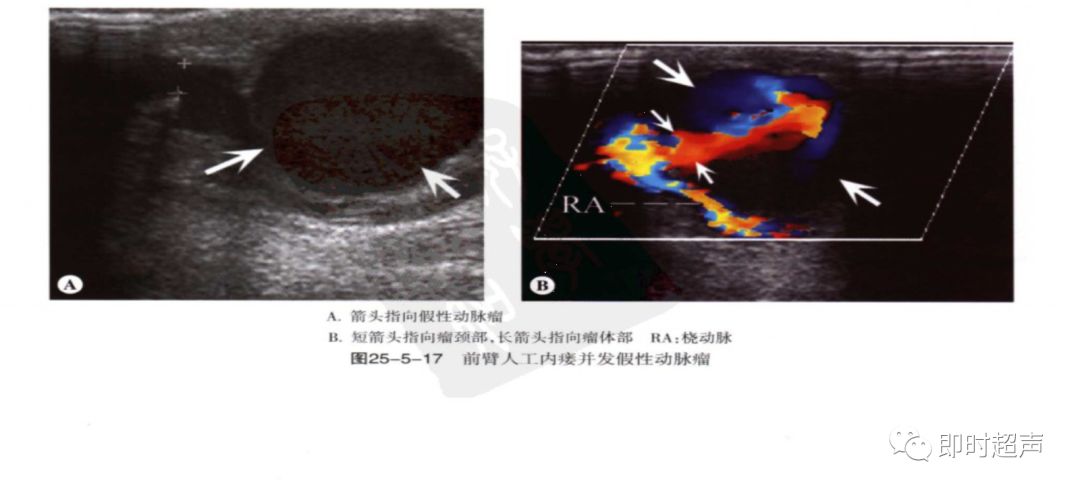

常见并发症-4

动脉瘤及静脉瘤样扩张